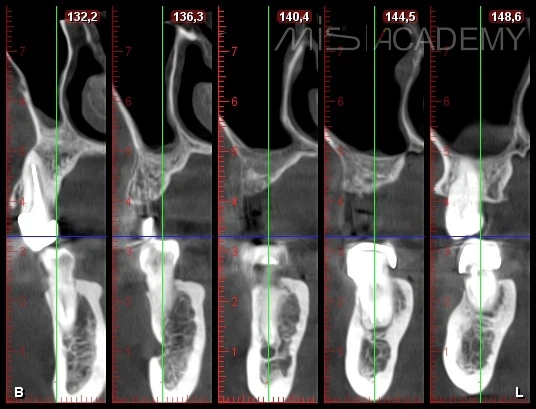

— Установка имплантата MIS C1 + CCT.

Вид через 4 месяца после имплантации.